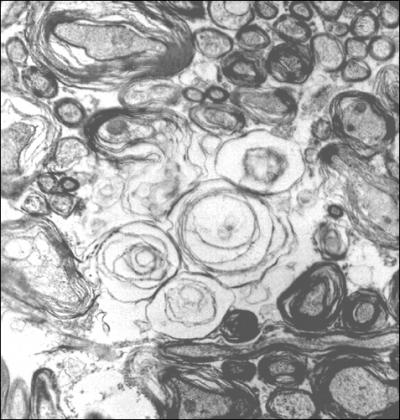

The researchers also discovered miswiring in the structure responsible for communications between the brain's left and right hemispheres, called the corpus collosum. Extensions of neurons, called axons, through which such long-distance communications are conducted, were deformed. A protective sheath, called myelin, that normally wraps and boosts axons' efficiency-- like insulation on an electrical wire – was reduced by one-third in the treated animals. This damage was three times worse in male than in female pups and would likely result in abnormal communication between the two hemispheres, say the researchers.